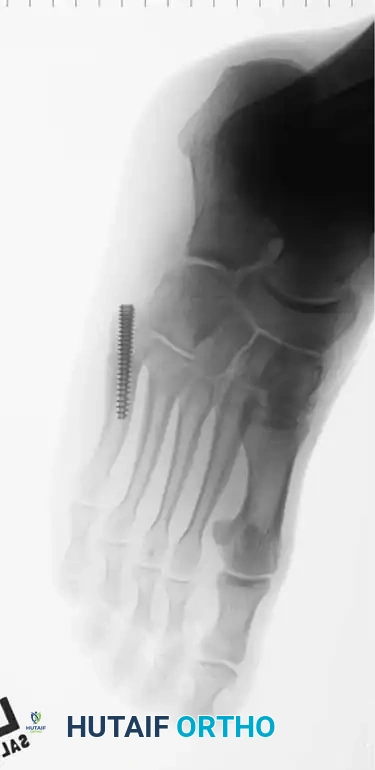

Fig. 86-45 A-C. Type IA (DeLee) fifth metatarsal fracture in a collegiate soccer player, representing an ideal candidate for early intramedullary fixation.

Fig. 86-45 A-C, Type IA (DeLee) fi fth metatarsal fracture in collegiate soccer player. D-F, After fi xation with variable pitch compression screw.

Fig. 86-45 D-F. Postoperative imaging after robust fixation utilizing a variable pitch compression screw, ensuring excellent compression across the fracture site.